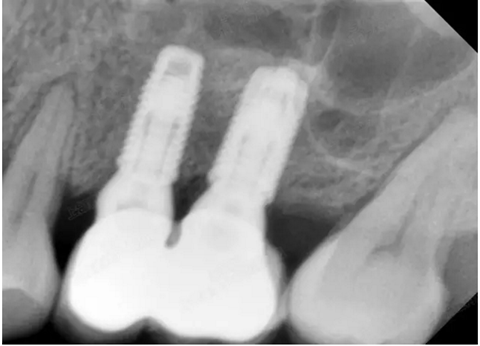

修復(fù)時(shí)根尖片

08.png

09.png

口內(nèi)照片

001.png

修復(fù)后一年

002.png